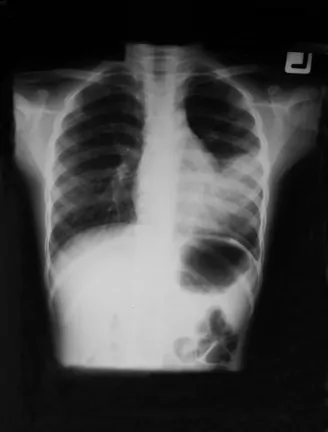

Lung of a child with Respiratory distress syndrome and left sided neumothorax